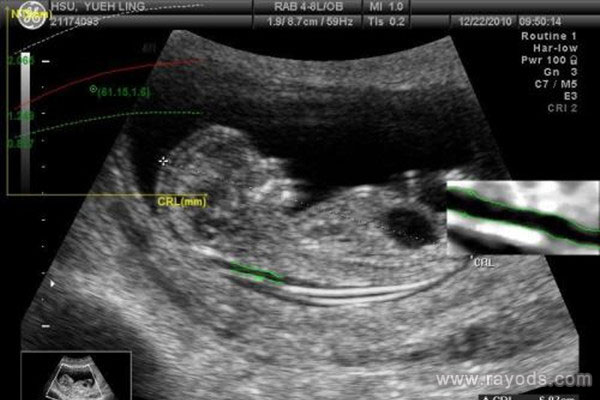

nt超声是从哪个部位检查?超声nt是检查什么?

nt超声是从哪个部位检查 怀孕之后需要做各种检查,甚至有的项目是以前从末检查过的。比如nt检查,许多孕妈妈感叹说,自己怀老大时没有做过nt检查,可是怀老二时医生就安排..